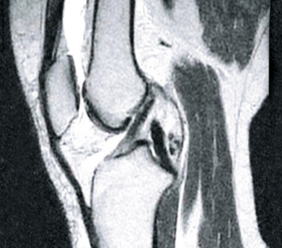

На снимката вляво можете да видите празни пространства в ставната капсула, образувани в резултат на прекомерна хидратация на тъканта. След терапия структурата на синовиалната течност се възстановява (снимката вдясно), възвръща своята вискоеластична консистенция и плъзгащи се свойства. Костите са правилно "смазани", така че да не се търкат една в друга, тъй като омекотяващите функции на ставата са възстановени.